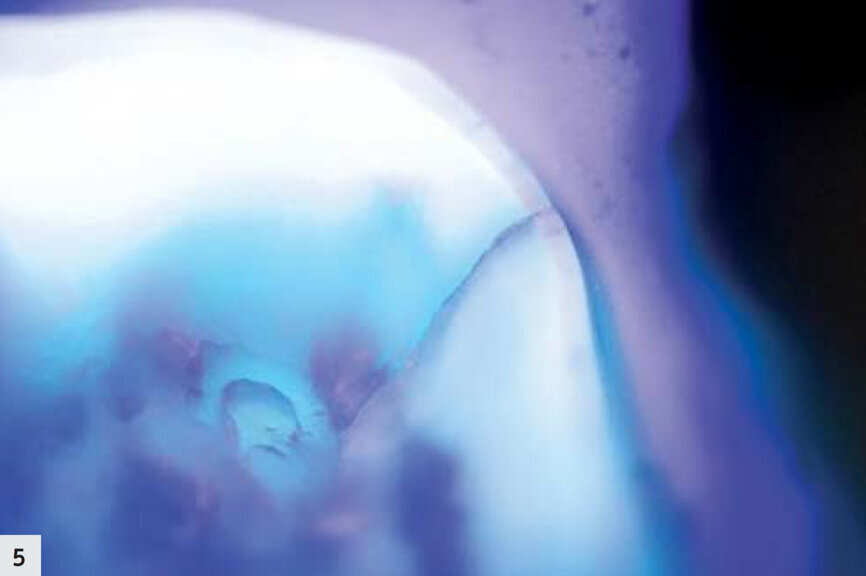

Figs. 4–5 : On peut observer une fissure très fine dont l’aspect est légèrement sombre ; aucune activité bactérienne n’est visible.

Les deux cas présentés par la suite illustrent comment le mode détection se révèle utile dans le cadre de votre pratique quotidienne. Un patient s’est présenté avec une ancienne restauration à l’amalgame défectueuse (Fig. 1). Après l’élimination de l’amalgame, des produits résultant de la corrosion et une fissure présente jusque dans la dentine ont été détectés dans la zone mésio-linguale ; l’aspect de la dentine environnante était légèrement plus sombre (Figs. 2–3). Sous le rayonnement proche-UV du mode détection, elle est apparue sous la forme d’une très fine ligne violette, due à la diffraction de la lumière au niveau de la fissure ; toutefois, la dentine environnante s’est révélée saine et sans métabolites bactériens, dans la mesure où aucune fluorescence rouge-orangée n’était observée (Figs. 4–5). Les cuspides ont été réduites afin de minimiser le risque d’une propagation de la fissure, mais aucune préparation supplémentaire n’a été nécessaire.